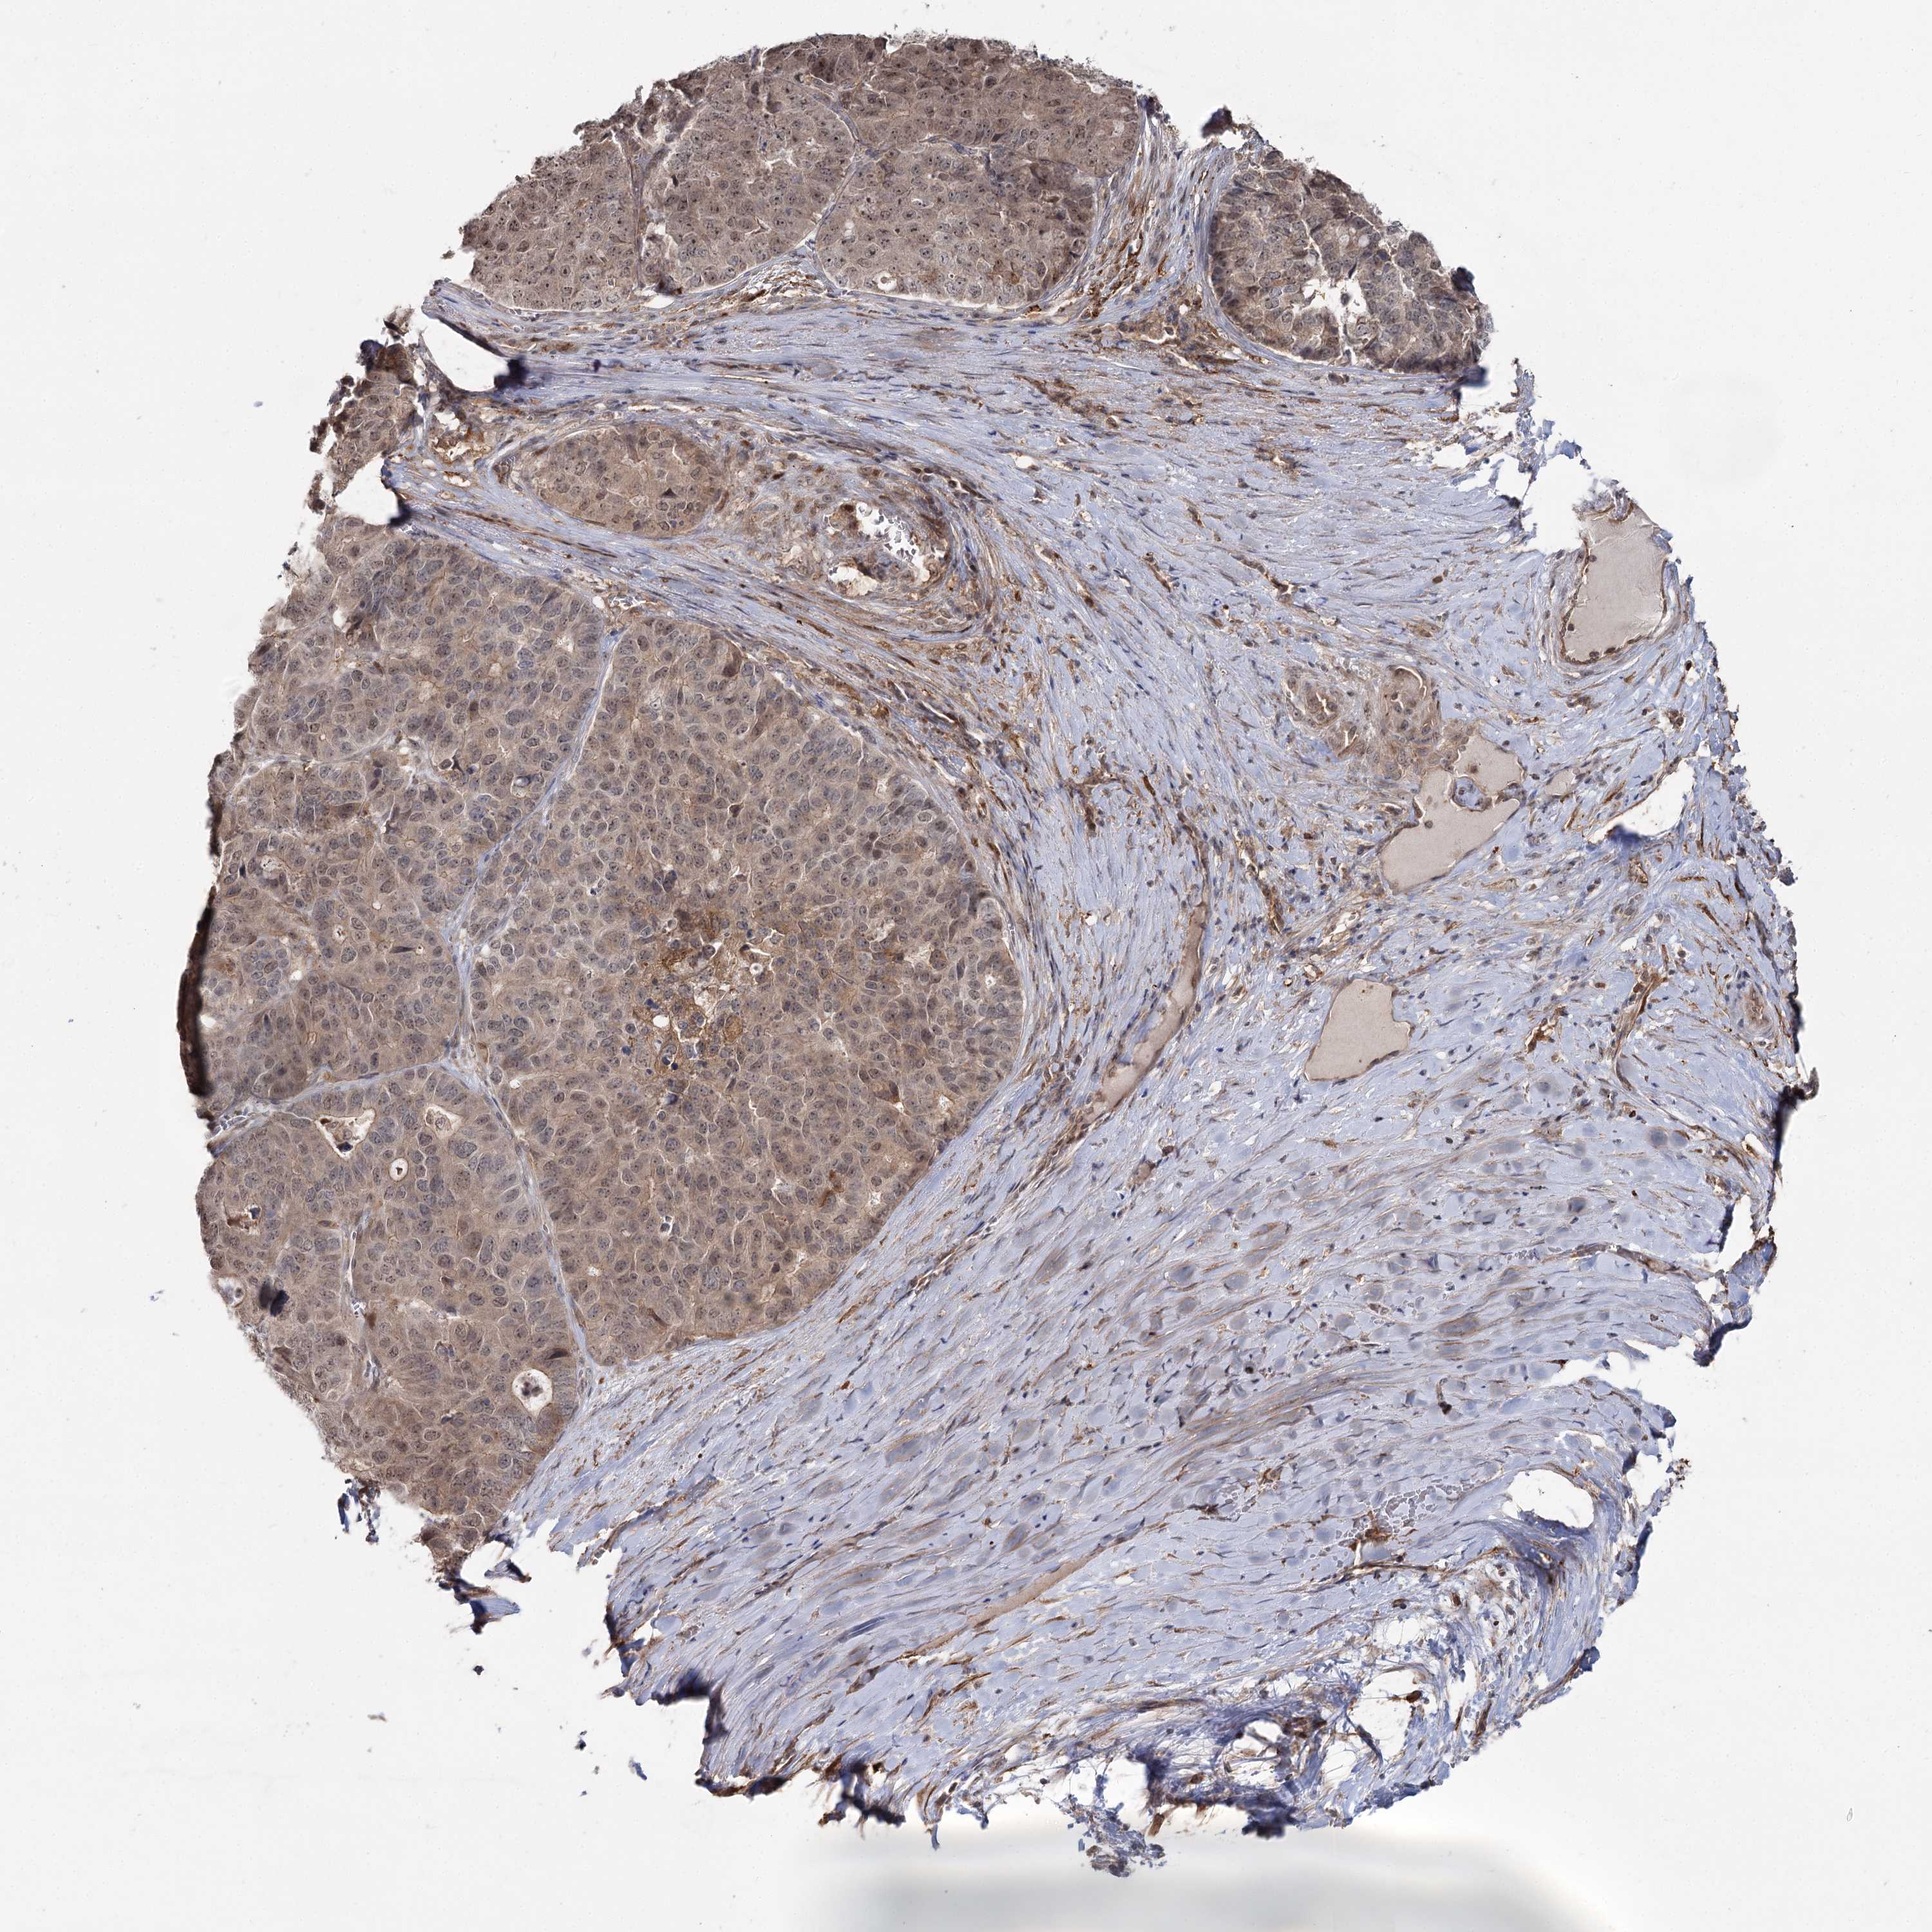

PANCREATIC CANCER - Protein expressioni

A mouse-over function shows sample information and annotation data. Click on an image to view it in a full screen mode. Samples can be filtered based on level of antibody staining by selecting one or several of the following categories: high, medium, low and not detected. The assay and annotation is described here.

Note that samples used for immunohistochemistry by the Human Protein Atlas do not correspond to samples in the TCGA dataset.

Antibody stainingi

Antibody staining in the annotated cell types in the current human tissue is reported as not detected, low, medium, or high, based on conventional immunohistochemistry profiling in selected tissues. This score is based on the combination of the staining intensity and fraction of stained cells.

Each image is clickable and will lead to virtual microscopy that enables deeper exploration of all samples and also displays staining intensity scores, fraction scores and subcellular localization as well as patient and tissue information for each sample.

Antibody HPA038084

Staining

High

Medium

Low

Not detected

Intensity

Strong

Moderate

Weak

Negative

Quantity

>75%

75%-25%

<25%

None

Location

Nuclear

Cytoplasmic/membranous

Cytoplasmic/membranous,nuclear

Adenocarcinoma, NOS